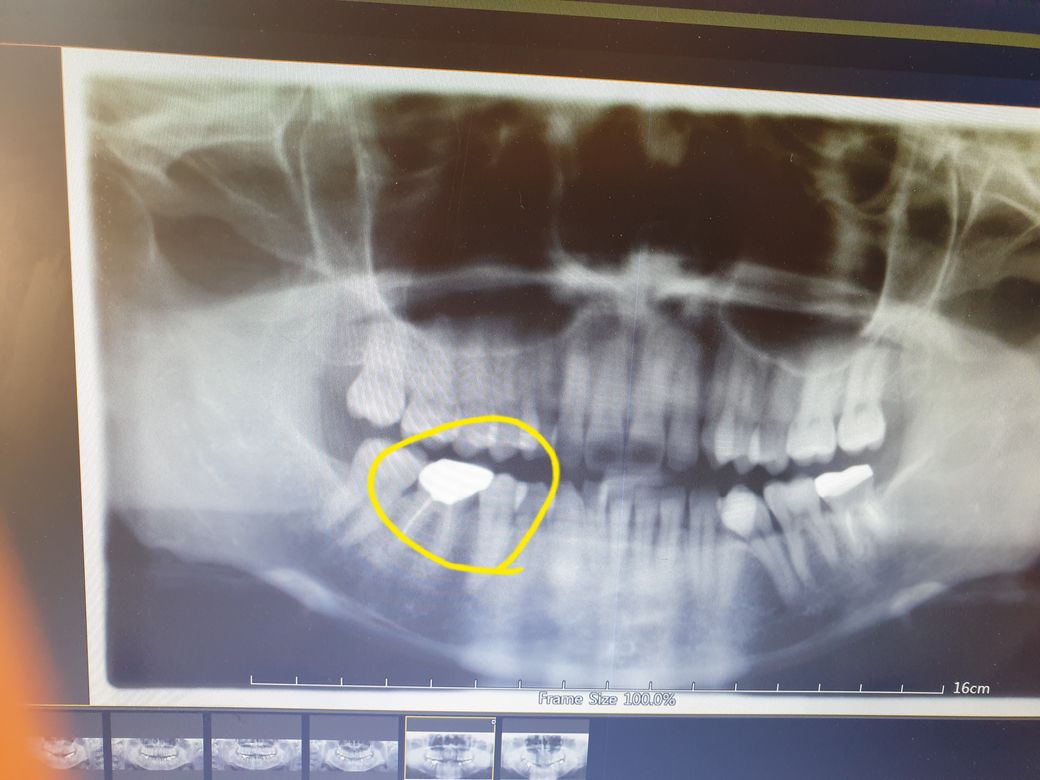

치아 엑스레이 사진상 보철을 새로 했는지요?

46번치아에 2012년 크라운한 후에 파노라마찌고

2015년 파노라마를 찍었습니다.

그사이에 다시 크라운을 떼어서 치료하지는 않았는데

사진상 보이는 부분이 다른거 같이 찍혀있어 문의드립니다. 같은 크라운인지요?

재치료는 분명히 안했는데 사진상 달라보여 문의드립니다

위에가 2015 년 아래가 2012년 사진입니다.

보철물의 모양은 사진을 찍은 각도에 따라서 다르게 보일 수 있습니다. 언뜻 봤을 경우에는 같은 보철물로 보입니다. 자세한 확인을 위해서 치과에서 진료를 받아보세요.

똑같아 보이는거 같습니다. 따로 크라운을 제거하고 새로 하신것같진 않아 보입니다. 엑스레이 상으로는 크라운 재료는 알수 없지만, 크게 달라 보이진 않습니다.

중간엔 치료를 전혀 하지 않았다면 같은 크라운이 맞습니다. 아래와 위의 사진이 다른 것은 해당 사진을 촬영하는 수평각 및 수직각 등이 다르기 때문에 일부 치아의 크기 및 크라운 모양 등이 달라 보일 수 있습니다.